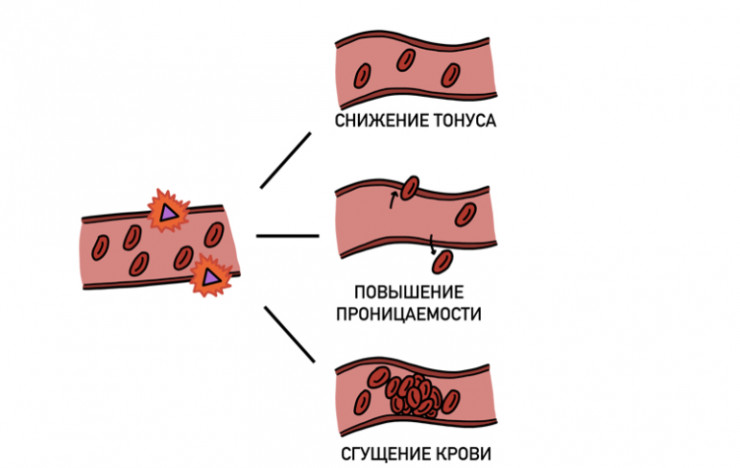

У трети больных с тяжелой формой COVID-19 цитокиновый шторм вызывает снижение тонуса сосудов, повышение их проницаемости, отеки и сгущение крови. Все это может вести к образованию опасных тромбов. Для борьбы с ними применяют так называемые антикоагулянты. В маленьких дозах антикоагулянты можно использовать и после выписки из больницы.